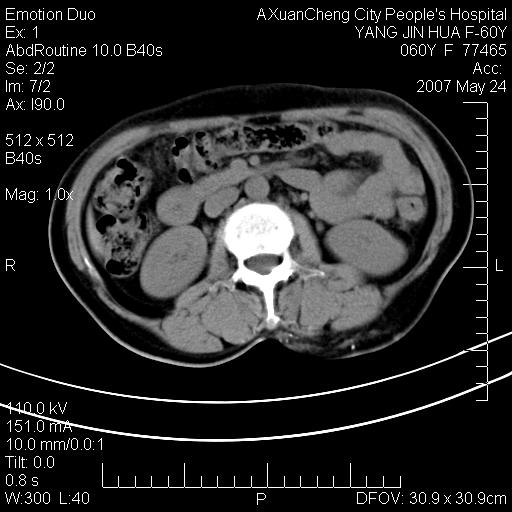

发现左侧腰背部包块40余年,逐渐长大,质软,局部表面可见扩张的血管影

左背部皮下良性肿瘤,密度不均,边界不清,内有脂肪、钙化,增强扫描无明显强化,血管平滑肌脂肪瘤?进一步诊断有困难,建议穿刺活检。

左侧背部皮下混杂密度肿块,结构较疏松,边缘欠光整,内有多发斑点状钙化,考虑:皮下血管瘤。

这个病理增强扫描之前,我们是考虑是血管瘤,可是现在增强后一点强化都没有,还能考虑是血管瘤吗